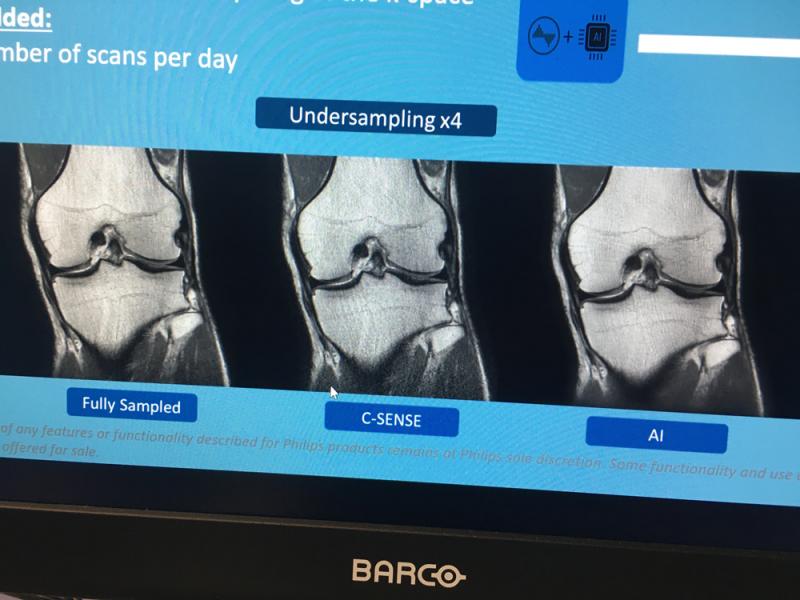

Here are images of some of the newest new medical imaging technologies displayed on the expo floor at the Radiological Society of North America (RSNA) 2019 meeting. Use the slider images below to see the photos.